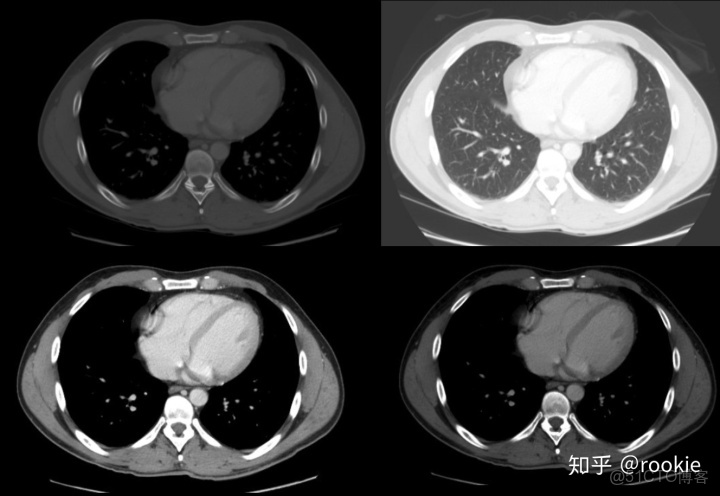

肺窗口窗口設置: (W:1600,L:-600)或(W:1500,L:-500)優點: 顧名思義,此窗口用於評估肺。靠近肺組織密度的高窗口水平(鑑於其低密度水平為低),並與寬窗口一起使用以提供良好的分辨率並可視化胸部的各種密度,例如肺實質以及相鄰的血管。

CLAHE算法增強局部對比度的X光圖像增強效果對比_#python 計算對比度_10

肺窗有助於評價肺,某些胸部病理學(如特定類型的結節)只能在這個窗口上看到。